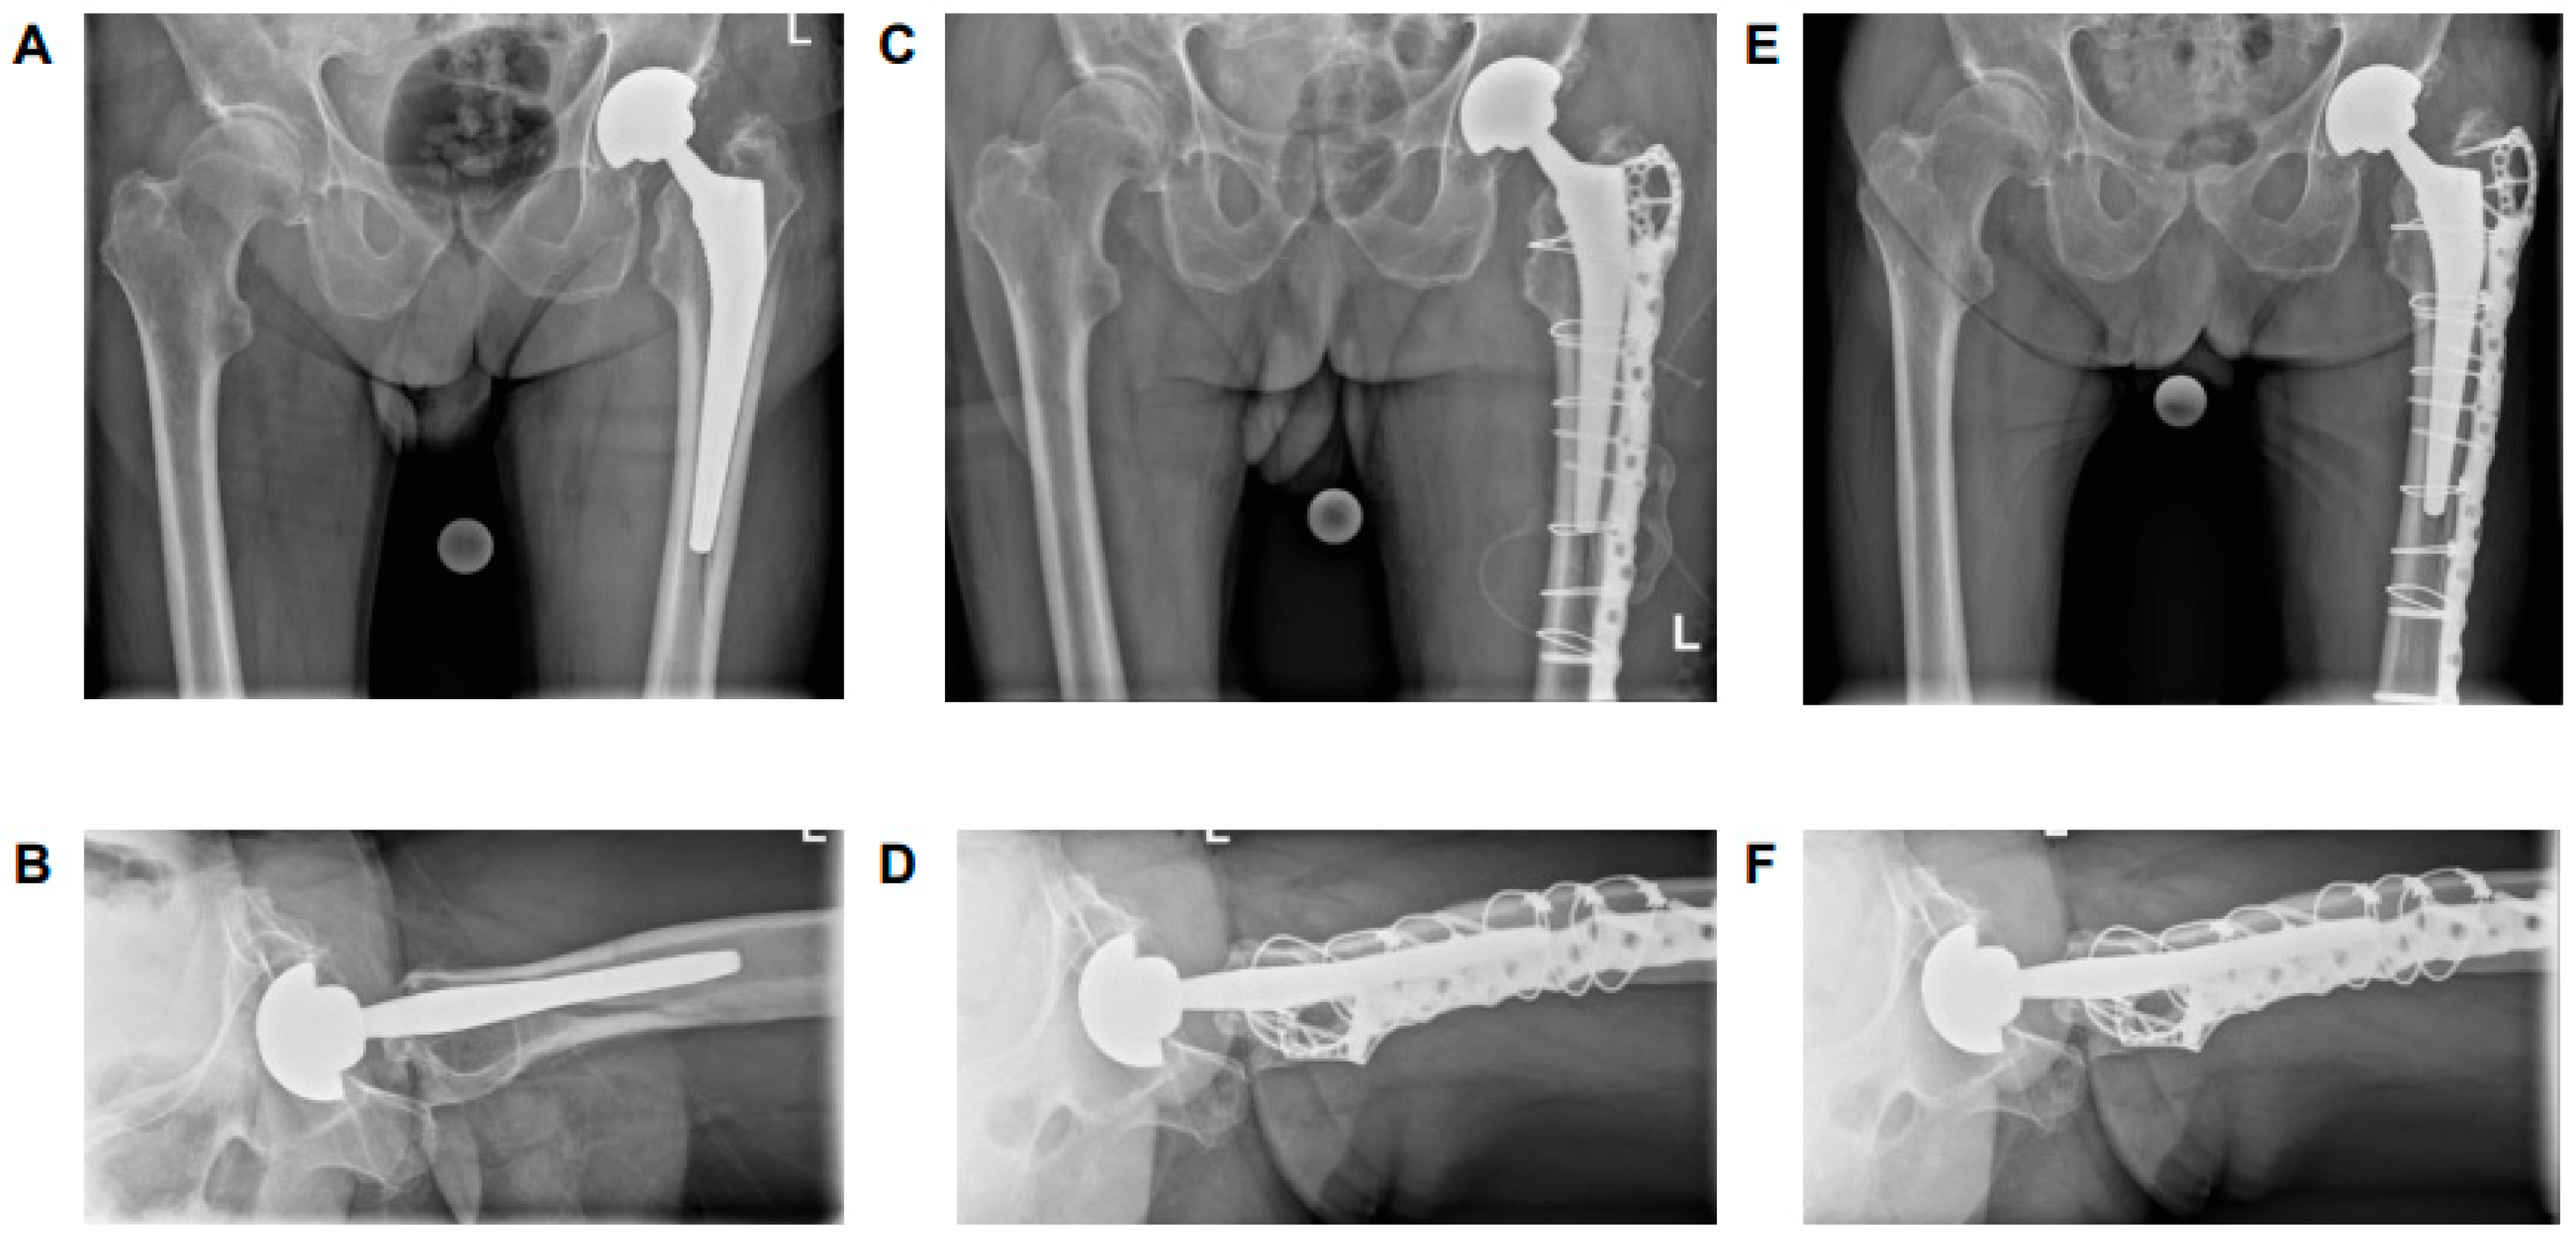

4.1. B2 ‘Stable’ Stems

4.2. B2 ‘Loose’ Stems